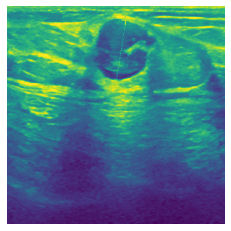

3.2 Breast Cancer Detection

Detection of breast cancer and its type is our second experiment. Breast UltraSound Images (BUSI) dataset [1] includes 222D ultrasound images collected from women between ages 252525 and 757575 years old in 201820182018. This dataset provides 780780780 single-channel grayscale ultrasound images categorized into 133133133 normal, and 647647647 cancer cases. We split the data into 50%percent5050\%, 25%percent2525\%, and 25%percent2525\% for training, validation, and test, respectively.

Results and Analysis: Table 2 shows the average accuracy, macro F1, and AUROC over 5 runs with different random initializations. We compare the performance of the methods on three different training sizes. However, unlike the dataset in section 3.1, there are much fewer samples in each setup in this dataset. The results show that Intelligent-Masking is much more superior in relatively smaller training annotations. We observe that Context Restoration shows lower results compared to Context Prediction which might be due to the fact that our classification tasks need the pre-trained network focus on the local structures like tumor regions rather than the global information. However, the loss of the Context Restoration is defined globally over the entire image unlike the Context Prediction and Intelligent-Masking that define the loss only over the masked regions.

In figure 3, we present qualitative examples of different masking strategies. It is observed that, unlike context prediction and restoration, our method tends to propose targeted masks like the tumor regions or regions with abnormalities and avoids masking less helpful regions. However, it should be noted that Intelligent-Masking does not necessarily mask the tumor regions but considers all areas of interest that results in better feature learning. Examples of other masking samples are provided in supplementary materials. Furthermore, in medical images, unlike natural scenes, the structures are very local with imbalanced information throughout an image. Therefore, random masking strategies as shown in Fig 3 operate ineffectively by masking non-informative regions.

Figure 2: Qualitative examples of compared method’s strategies for masking

Figure 3: More qualitative examples of different distorting strategies including our method. We show the different self-supervised mechanisms on both datasets of MR (rows: 1-3) and ultrasound (rows: 4-6) images for lower-grade glioma and breast cancer diagnosis respectively. We include both images of normal (rows: 1,4) and cancer (rows: 2,3,5,6) conditions for each dataset. We also observe that our method treats each image based on its context information with no predetermined strategy.